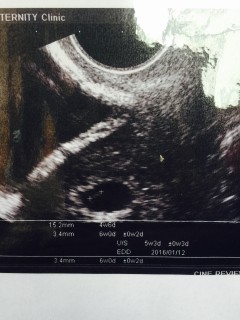

• おなまえmiiyann

• ねんれい19

• 妊娠週5w3d

7月に着床しきれず科学流産してました(´°̥̥̥̥̥̥̥̥ω°̥̥̥̥̥̥̥̥`) 11月19日陽性反応でて 5w4dに初診しに行きました! おー!妊娠してるね~って言われました٩('ω')و ニヤニヤ止まりませんでした(笑) 次は2週間後に心拍確認します! baby頑張れ(*˙︶˙*)☆*°